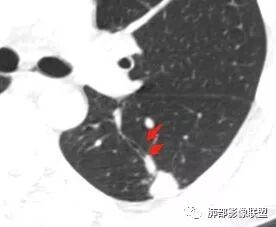

左肺下叶背段孤立结节,长轴与胸膜平行,支气管近端截断,刀削平直,糊墙,卫星灶轻强化,考虑TB。

左肺下叶背段小结节 ,糊墙 ,胸膜外脂肪间隙增宽 ,引流支气管壁厚 ,有爬行征 ,病灶无明显强化,考虑结核可能。

左肺下叶病变,边缘平直,似有U形凹陷,树芽及卫星病灶,支气管爬行征?无明显强化,考虑结核。